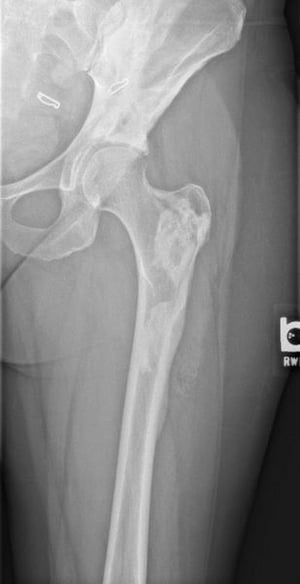

このX線写真には,39歳の患者の大腿骨に生じたメロレオストーシスの「dripping candle wax」像が写っている。

Image courtesy of Michael J. Joyce, MD, and David M.Joyce, MD.